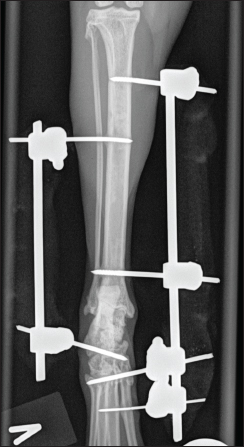

The fracture was stabilized with a unilateral biplanar trans articular external fixator [External skeletal fixator (ESF) type 1b], using small treaded Elis pins, the Kirscher–Ehmer plus system (Veterinary instrumentation, Sheffield) drilled into the tibia, tarsal and proximal metatarsals through stab incisions, as previously described techniques for pin placements (Palmer, 1999; Kraus et al., 2003), using a battery-driven drill (Colibri II, Depuy Synths). The external fixation bars were contoured to approximately 125.

Fig. 2. (A and B) Mediolateral and craniocaudal digital radiograph of the left hock joint eight weeks post-operative. The fracture line was well visible. The lateral frame was removed at this stage.

Eight weeks postoperatively, the cat was back for re-examination and radiographs. The owner reported that the cat moved freely around the house after 6 weeks of cage rest. The cat was anesthetized as previously, orthogonal radiographs revealed good fracture healing (Fig. 2a and 2b), and the lateral frame was removed according to standard procedures (Kraus et al., 2003). Twelve weeks postoperatively, the cat was back for re-examination and radiographs, and the owner could report that the cat was doing fine. The cat was anesthetized as previously for orthogonal radiographs, which revealed good fracture healing, and the medial frame was removed. A set of new orthogonal radiographs was taken after frame removal. Palpation of the affected talocrural joint revealed a moderately reduced range of motion (ROM) compared to the opposite joint. Measurements with a goniometer showed left extension at 160°, flexion at 67°, right extension at 167°, and flexion at 20° (Jaeger et al., 2007). Thirty-three weeks postoperatively, the cat was seen for a progress check. The cat was still not allowed outdoors. Slight lameness was evident when the cat moved freely on the floor. There was no pain or swelling in the affected area during palpation, and the ROM had improved, but it was still reduced compared to the opposite limb (left extension 163° and flexion 30°). The cat was anesthetized as previously for orthogonal radiographs (Fig. 3a and 3b).